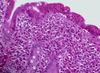

What is seen here?

Viral esophagitis (typical of herpes):

- Margination of chromatin

- Nuclear molding

- Multinucleate

Also ground glass appearance of nuclei